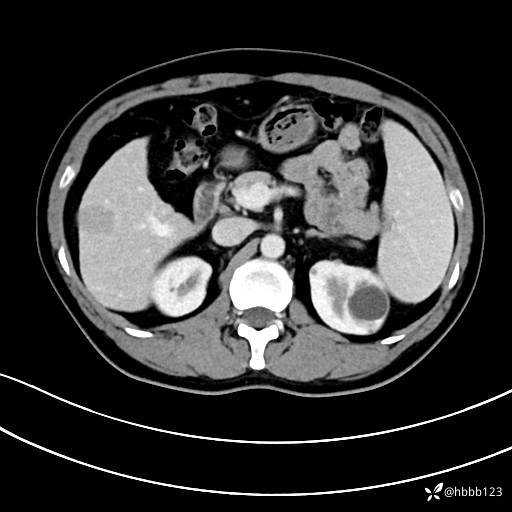

门诊完善上腹部CT平扫+增强。

延迟期:

典型的”****“特征!你能秒杀吗?